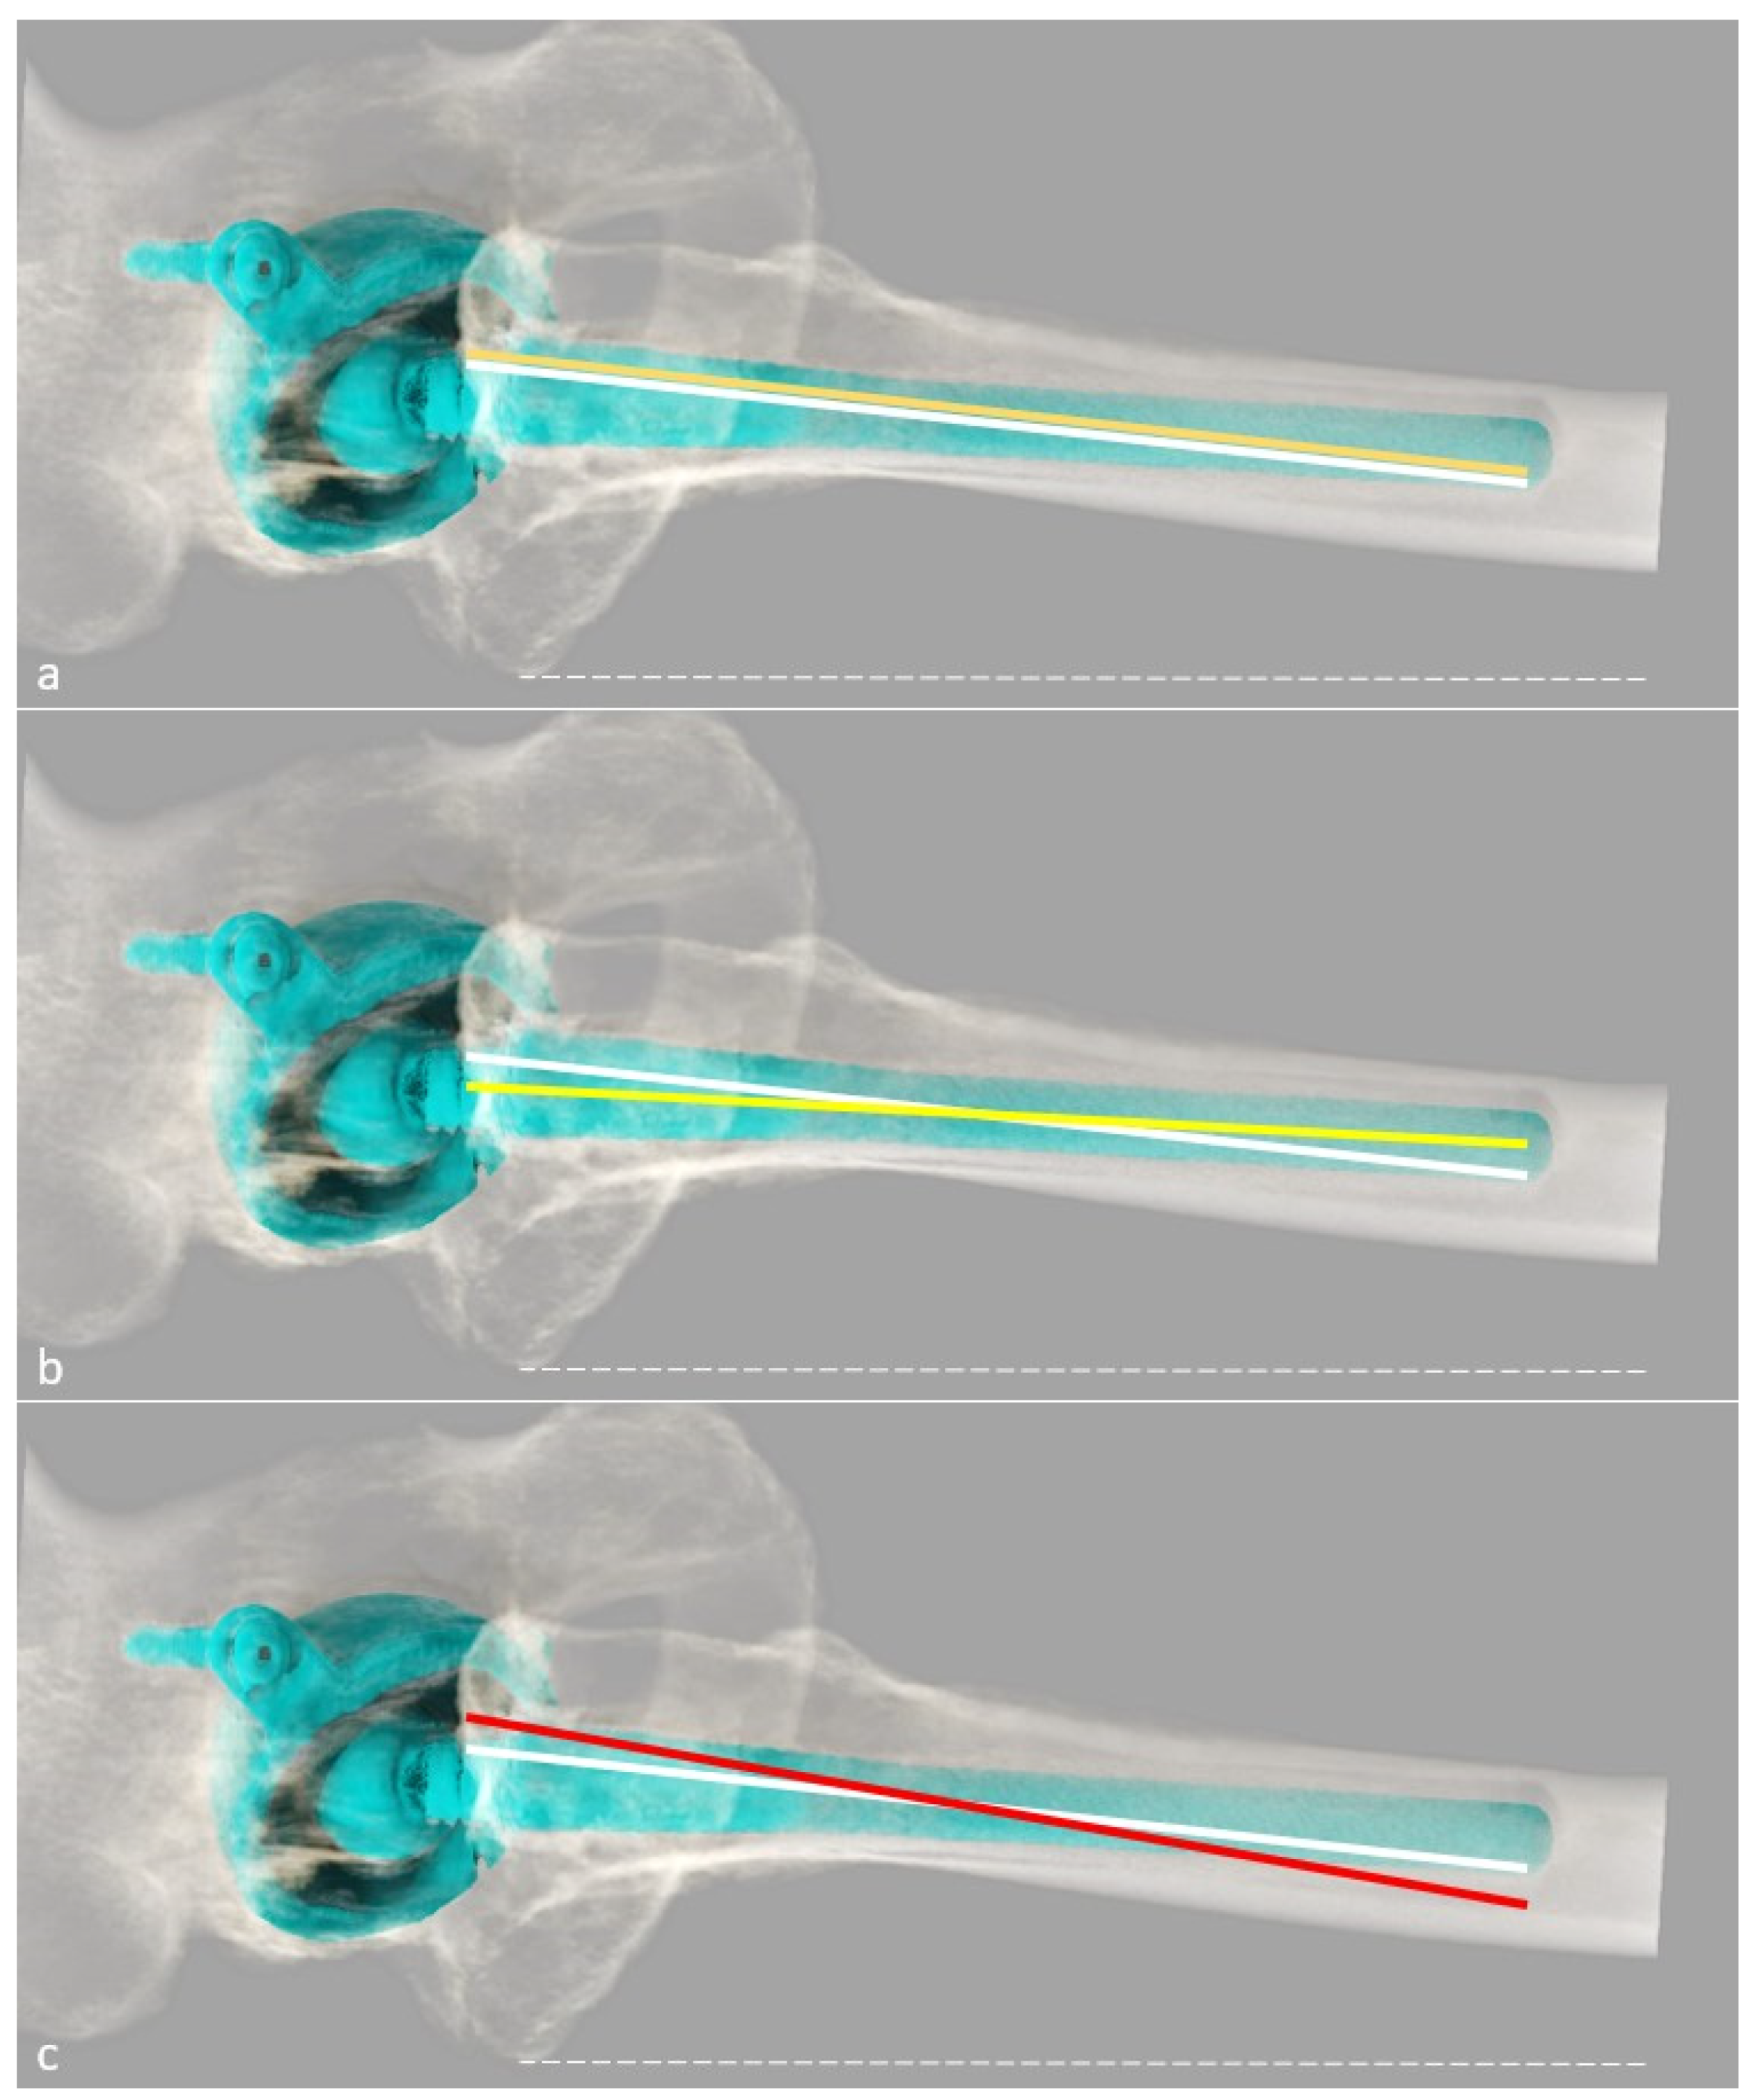

2.2.2. Types of Architectural Deformities and Their Implications

- the hip can be classified as mentioned above (e.g., centered, medialized, lateralized, proximalized, or proximo-lateralized);

- (2)

- the pre-arthritic centers of the femoral head and acetabulum must be determined (potentially using the contralateral hip if healthy), and the optimal diameter of the acetabular cup measured on a transverse CT slice, so that its template can be positioned at the level of the true acetabular floor medially and of the subchondral bone proximally, slightly superior and medial to the center of the native acetabulum to simulate reaming;

- (3)

- the stem size and model can be determined, such that the templated head center can match the templated cup center craniocaudally, with the native mediolateral center maintained original even if pathologic, except in case of medialized head, which has to match templated cup center in both axis [60].